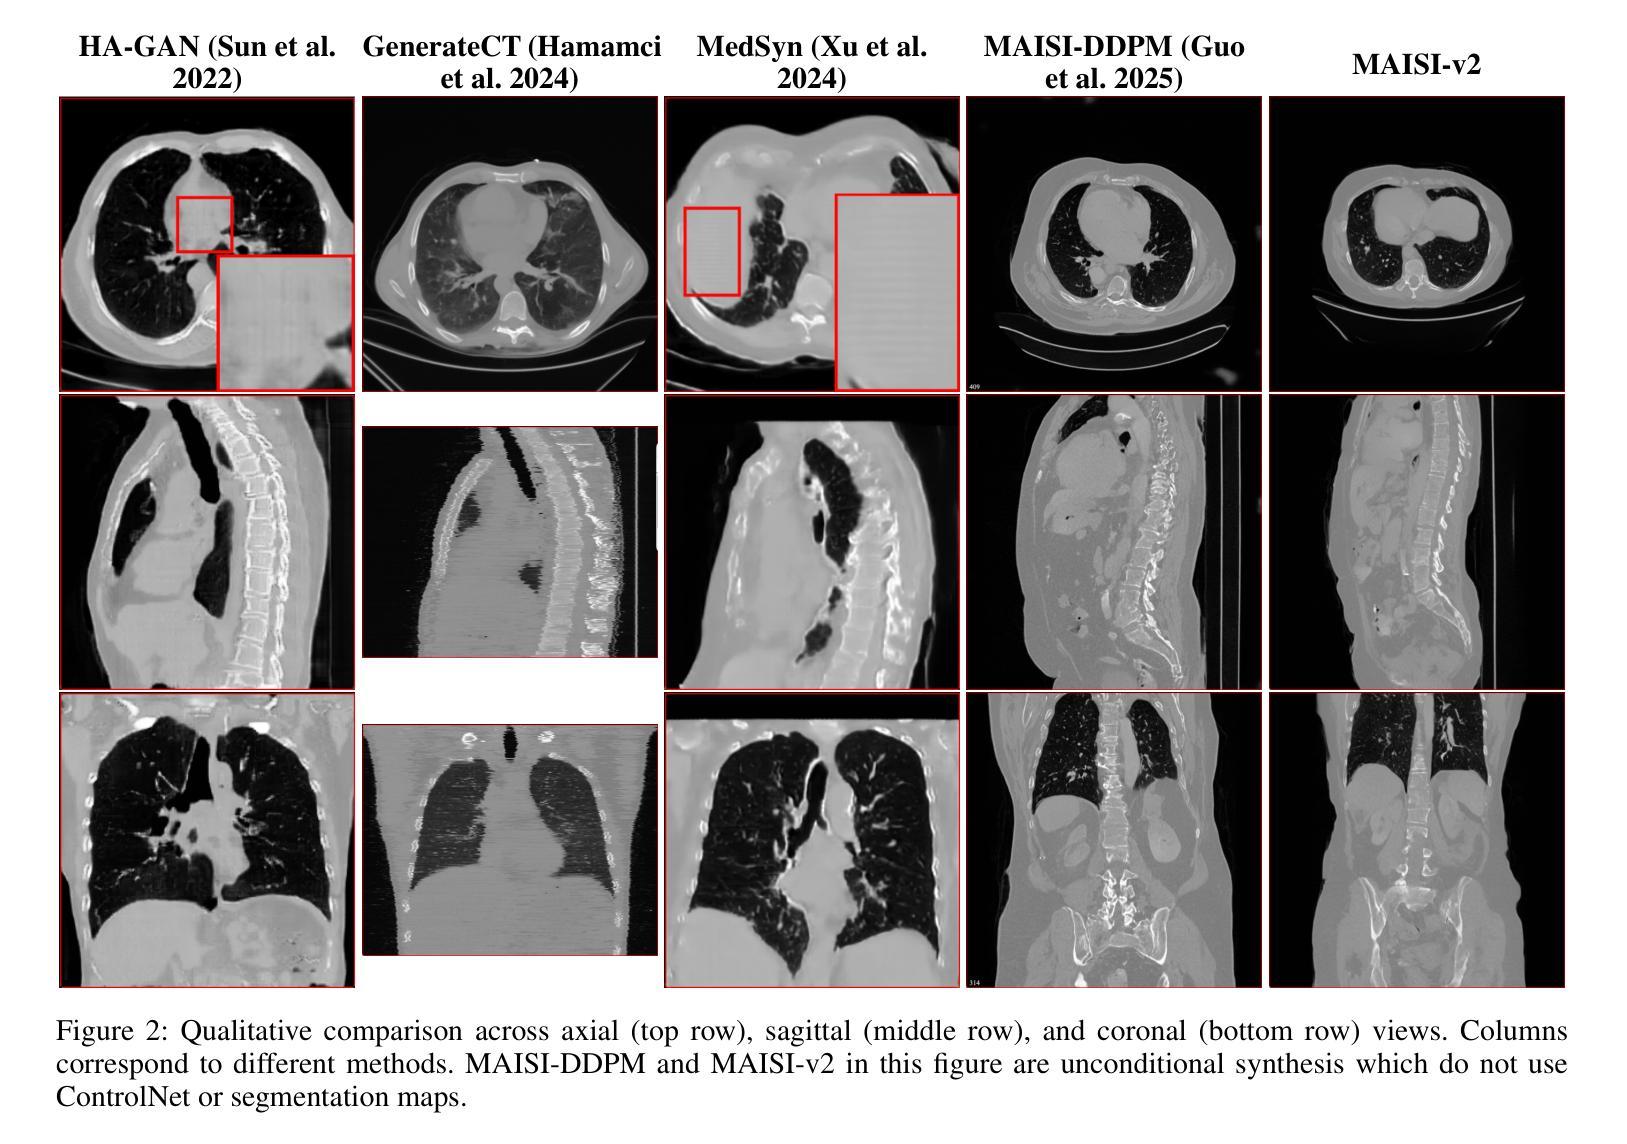

MAISI-v2: Accelerated 3D High-Resolution Medical Image Synthesis with Rectified Flow and Region-specific Contrastive Loss

Medical image synthesis is an important topic for both clinical and research applications. Recently, diffusion models have become a leading approach in this area. Despite their strengths, many existing methods struggle with (1) limited generalizability that only work for specific body regions or voxel spacings, (2) slow inference, which is a common issue for diffusion models, and (3) weak alignment with input conditions, which is a critical issue for medical imaging. MAISI, a previously proposed framework, addresses generalizability issues but still suffers from slow inference and limited condition consistency. In this work, we present MAISI-v2, the first accelerated 3D medical image synthesis framework that integrates rectified flow to enable fast and high quality generation. To further enhance condition fidelity, we introduce a novel region-specific contrastive loss to enhance the sensitivity to region of interest. Our experiments show that MAISI-v2 can achieve SOTA image quality with $33 \times$ acceleration for latent diffusion model. We also conducted a downstream segmentation experiment to show that the synthetic images can be used for data augmentation. We release our code, training details, model weights, and a GUI demo to facilitate reproducibility and promote further development within the community.

医学图像合成是临床和研究应用中的一个重要课题。最近,扩散模型已成为该领域的主流方法。尽管它们具有优势,但许多现有方法仍面临(1)通用性有限,仅适用于特定部位或体素间距;(2)推理速度慢,这是扩散模型的常见问题;(3)与输入条件的对齐较弱,这对医学影像来说是关键问题。之前提出的MAISI框架解决了通用性问题,但仍存在推理速度慢和条件一致性有限的问题。在这项工作中,我们推出了MAISI-v2,这是第一个加速的3D医学图像合成框架,它整合了校正流,以实现快速和高质量的生成。为了进一步提高条件保真度,我们引入了一种新型的区域特异性对比损失,以提高对感兴趣区域的敏感性。我们的实验表明,MAISI-v2可以在潜在扩散模型上实现$33 \times$的加速,同时达到最先进的图像质量。我们还进行了下游分割实验,以证明合成图像可用于数据增强。我们发布了我们的代码、训练细节、模型权重和GUI演示,以促进社区内的可重复性和进一步发展。

Summary

医疗图像合成是临床和研究应用的重要课题,近期扩散模型成为该领域的主流方法。但现有方法存在通用性有限、推理速度慢以及与输入条件对齐不佳等问题。MAISI-v2是首个加速的3D医疗图像合成框架,通过整合矫正流实现快速、高质量生成。为提高条件保真度,引入区域特定对比损失以增强对感兴趣区域的敏感性。实验显示,MAISI-v2可在潜在扩散模型上实现$33 \times$加速,同时保持图像质量。此外,进行下游分割实验证明合成图像可用于数据增强。